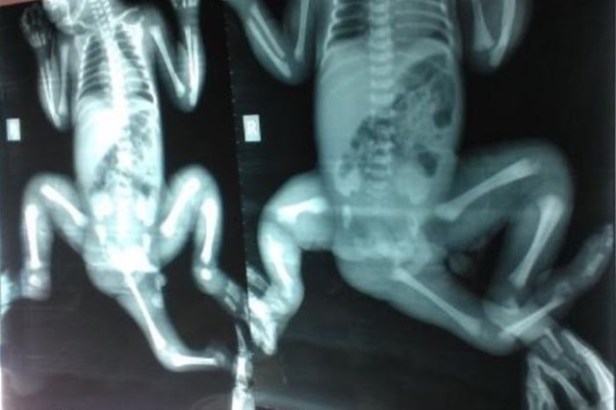

Choity Khatun was born in a village in Bangladesh with a condition called cordial twinning, which meant she had part of a twin develop in her perineum.

Professor Kimber said they had to reconstruct many parts of Choity’s anatomy, as she had double of some organs, and many were attached in the wrong place inside her lower body.